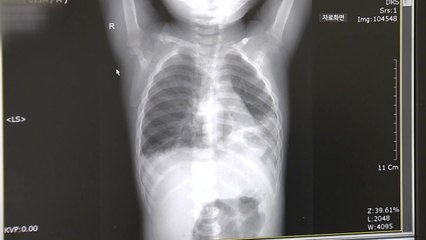

소아의료체계 붕괴로 인해 중증·응급 진료 장비가 부족한 아동병원이 3차 병원에서 해야 할 소아응급실 역할까지 수행하고 있다는 설문 결과가 나왔습니다. <br /> <br />대한아동병원협회는 회원 아동병원 50곳을 설문 조사한 결과 아동병원 90%가 소아응급실의 대체 역할을 수행하는 것으로 나타났다고 밝혔습니다. <br /> <br />한 달에 구급차로 들어오는 응급 환자 수가 5명 이하라고 답한 경우는 56%였고, 6명에서 10명 사이는 22%, 11명에서 15명이 4%였고, 16명 이상도 6%나 됐습니다. <br /> <br />아동병원 한 곳은 구급차로 이송된 소아 응급 환자가 120명에 달하기도 했습니다. <br /> <br />또, 아동병원 10곳 중 7곳은 소아 응급환자를 소아응급의료센터 등 상급종합병원에 전원하는 데에도 큰 어려움을 겪는 것으로 나타났습니다. <br /> <br />아동병원협회는 대형병원에서 소아 응급실을 폐쇄하는 등 전반적인 소아의료체계가 붕괴하면서, 응급·중증 진료 시스템이 구축돼있지 않는 아동병원이 소아응급실 역할까지 맡아야 하는 처지가 됐다고 설명했습니다. <br /> <br /> <br /><br /><br />YTN 홍선기 (sunki0524@ytn.co.kr)<br /><br />※ '당신의 제보가 뉴스가 됩니다' <br />[카카오톡] YTN 검색해 채널 추가 <br />[전화] 02-398-8585 <br />[메일] social@ytn.co.kr<br /><br />▶ 기사 원문 : https://www.ytn.co.kr/_ln/0103_202406302211549200<br />▶ 제보 안내 : http://goo.gl/gEvsAL, 모바일앱, social@ytn.co.kr, #2424<br /><br />▣ YTN 데일리모션 채널 구독 : http://goo.gl/oXJWJs<br /><br />[ 한국 뉴스 채널 와이티엔 / Korea News Channel YTN ]